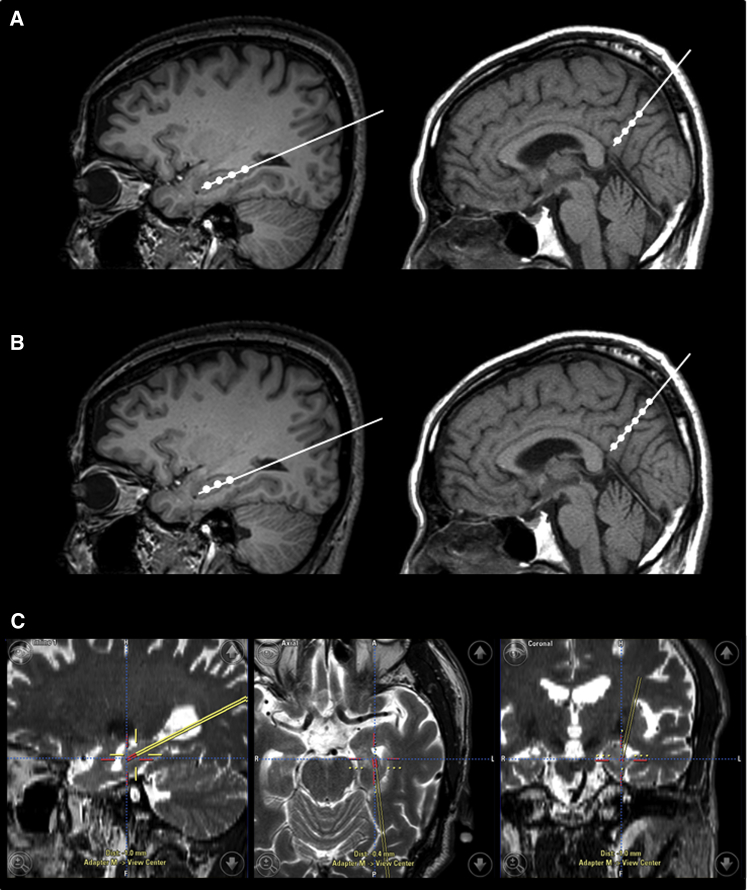

臍帶間充質(zhì)干細(xì)胞的立體定向給藥

- (A)術(shù)中導(dǎo)航引導(dǎo) hUCB-MSC 立體定向給藥。在縮回套管的同時(shí),沿插入軌跡將 hUCB-MSC 注射到左右海馬和右楔前葉的四個(gè)部位(間隔 5 毫米)

- (B)然而,在九名患者中,有六名患者的第四次注射位于側(cè)腦室顳角,這可能是由于海馬嚴(yán)重萎縮所致。在這些情況下,省略的劑量被注射到右楔前葉,導(dǎo)致每個(gè)海馬有三個(gè)注射部位,右楔前葉有六個(gè)注射部位。

- (C)將 hUCB-MSC 立體定向注射到左海馬的示例